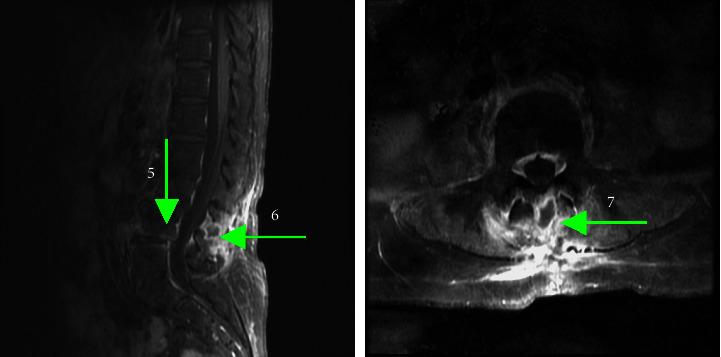

() is a pink-pigmented, aerobic, nonfermentative, slow-growing Gram-negative coccus typically isolated from the natural environment, human skin, and hospital environment. This pathogen, in most circumstances, leads to infections in immunocompromised hosts, but it may sometimes invade immunocompetent individuals. Bacteraemia is the most common form of infection caused by . In contrast, only two case reports have described -related epidural abscess formation and infective spondylitis. In this case report, we shared the history and treatment experience of a 76-year-old female who was diagnosed with infective spondylitis and epidural abscess caused by . She received a local transdermal injection into the lower back to relieve her back pain two months before symptom onset, which was considered to be associated with this infection episode. After admission to the hospital, neurosurgeons performed emergent decompression and debridement. She was treated with intravenous ceftriaxone for four weeks, followed by oral ciprofloxacin for another eight weeks. The patient recovered well without any sequelae and had no relapse of infection at least six months after the end of treatment. In addition to the case report, we reviewed the literature for reported cases caused by . Our experience suggests that clinicians should include as one of the possible healthcare-associated pathogens among individuals who have undergone transdermal procedures. We believe that this article will help clinicians better recognize infection.

(某病原体名称)是一种粉红色色素沉着、需氧、非发酵、生长缓慢的革兰氏阴性球菌,通常从自然环境、人体皮肤和医院环境中分离出来。这种病原体在大多数情况下会导致免疫功能低下宿主感染,但有时也可能侵袭免疫功能正常的个体。菌血症是由该病原体引起的最常见感染形式。相比之下,仅有两例病例报告描述了与该病原体相关的硬膜外脓肿形成和感染性脊柱炎。在本病例报告中,我们分享了一名76岁女性的病史和治疗经验,她被诊断为由该病原体引起的感染性脊柱炎和硬膜外脓肿。在症状出现前两个月,她接受了下背部局部经皮注射以缓解背痛,这被认为与此次感染事件有关。入院后,神经外科医生进行了紧急减压和清创术。她接受了四周的静脉注射头孢曲松治疗,随后又口服环丙沙星八周。患者恢复良好,无任何后遗症,治疗结束后至少六个月无感染复发。除了该病例报告外,我们还查阅了有关该病原体所致病例的文献。我们的经验表明,临床医生应将该病原体列为接受经皮操作个体中可能的医疗相关病原体之一。我们相信本文将有助于临床医生更好地认识该病原体感染。